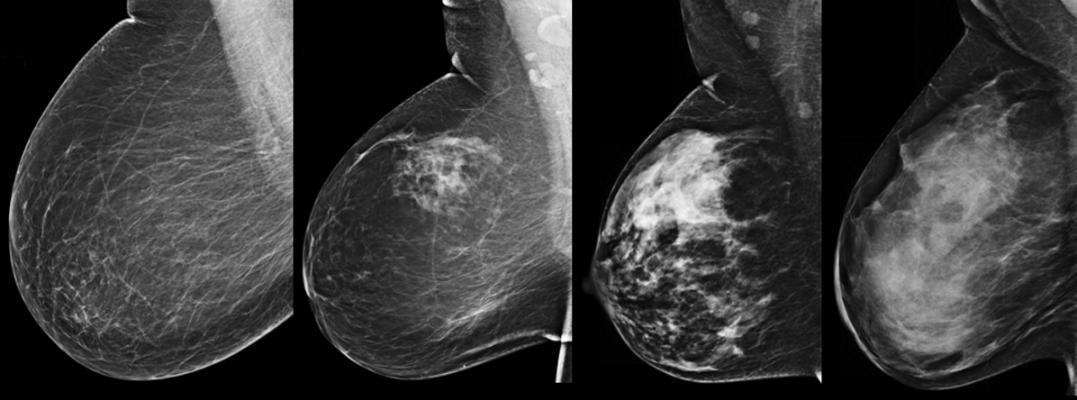

The study included 771 breast cancers (652 screen-detected and 119 interval cancers) diagnosed at EWBC between 2009 and 2012. Breast density was assessed using both the ACR BI-RADS 4th Edition and VolparaDensity, a commercially available software tool. VolparaDensity automatically generates an objective measurement of volumetric breast density as both a continuous percentage and as Volpara Density Grades (VDG), which correspond to the BI-RADS density categories. Mammographic sensitivity was compared between the density assessment methods and within each VDG category, by dividing each category into “high” and “low” using the volumetric breast density mid-point of each VDG.

Overall, mammographic sensitivity in the study cohort was 85 percent. Across visual BI-RADS categories, fatty replaced to extremely dense, mammographic sensitivity was 82 percent, 90 percent, 84 percent and 66 percent, respectively. Using VolparaDensity categories, mammographic sensitivity was 95 percent, 89 percent, 83 percent and 65 percent across VDG categories 1-4, respectively. The linear relationship between mammographic sensitivity and breast density was stronger when using the automated VDG categories than when using visually-assigned BI-RADS categories.

In addition, the results also demonstrated that there was a wide range in mammographic sensitivity within density categories. This suggests that important information relating to masking risk may be missed using BI-RADS categories. While sensitivity was similar for women at the lower and upper end of the VDG1 and VDG2 categories, sensitivity decreased significantly between low and high VDG3 women (i.e. decreased from 86 percent to 77 percent) and low and high VDG4 women (i.e. decreased from 72 percent to 58 percent). Additionally, women with extremely dense breasts (VDG4) category were 4.7 times as likely as women with fatty breasts (VDG1 or VDG2) breasts to have a diagnosis of interval cancer versus screen-detected cancer.